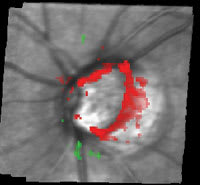

Clinical Impression The HRT detected glaucomatous damage in 1994 while the visual field was still normal. Over the following 12 years, the visual field showed fluctuation but it was not until 2006 that a repeatable visual defect could be confirmed. Progressive structural damage was also detected by the HRT. In this case, the HRT was able to detect damage earlier than conventional methods and also detected progressive structural change before the visual field showed a confirmed defect. |

Figure. The Progression Analysis OS. HRT shows large areas of significant change starting in 2001. |